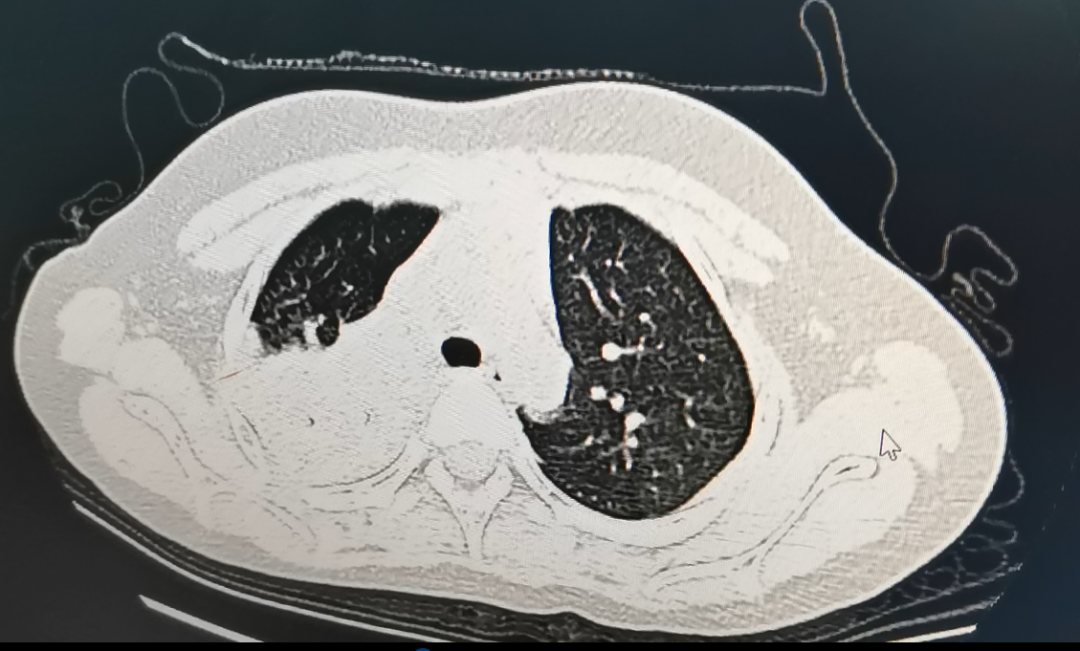

经由CT搜检发现

她传染了肺炎支原体

肺部酿成了“白”肺

经由大夫搜检,孩子整个右肺大部门已经酿成了白肺状,肺部存在病灶,经由检测确诊为支原体肺炎的传染。